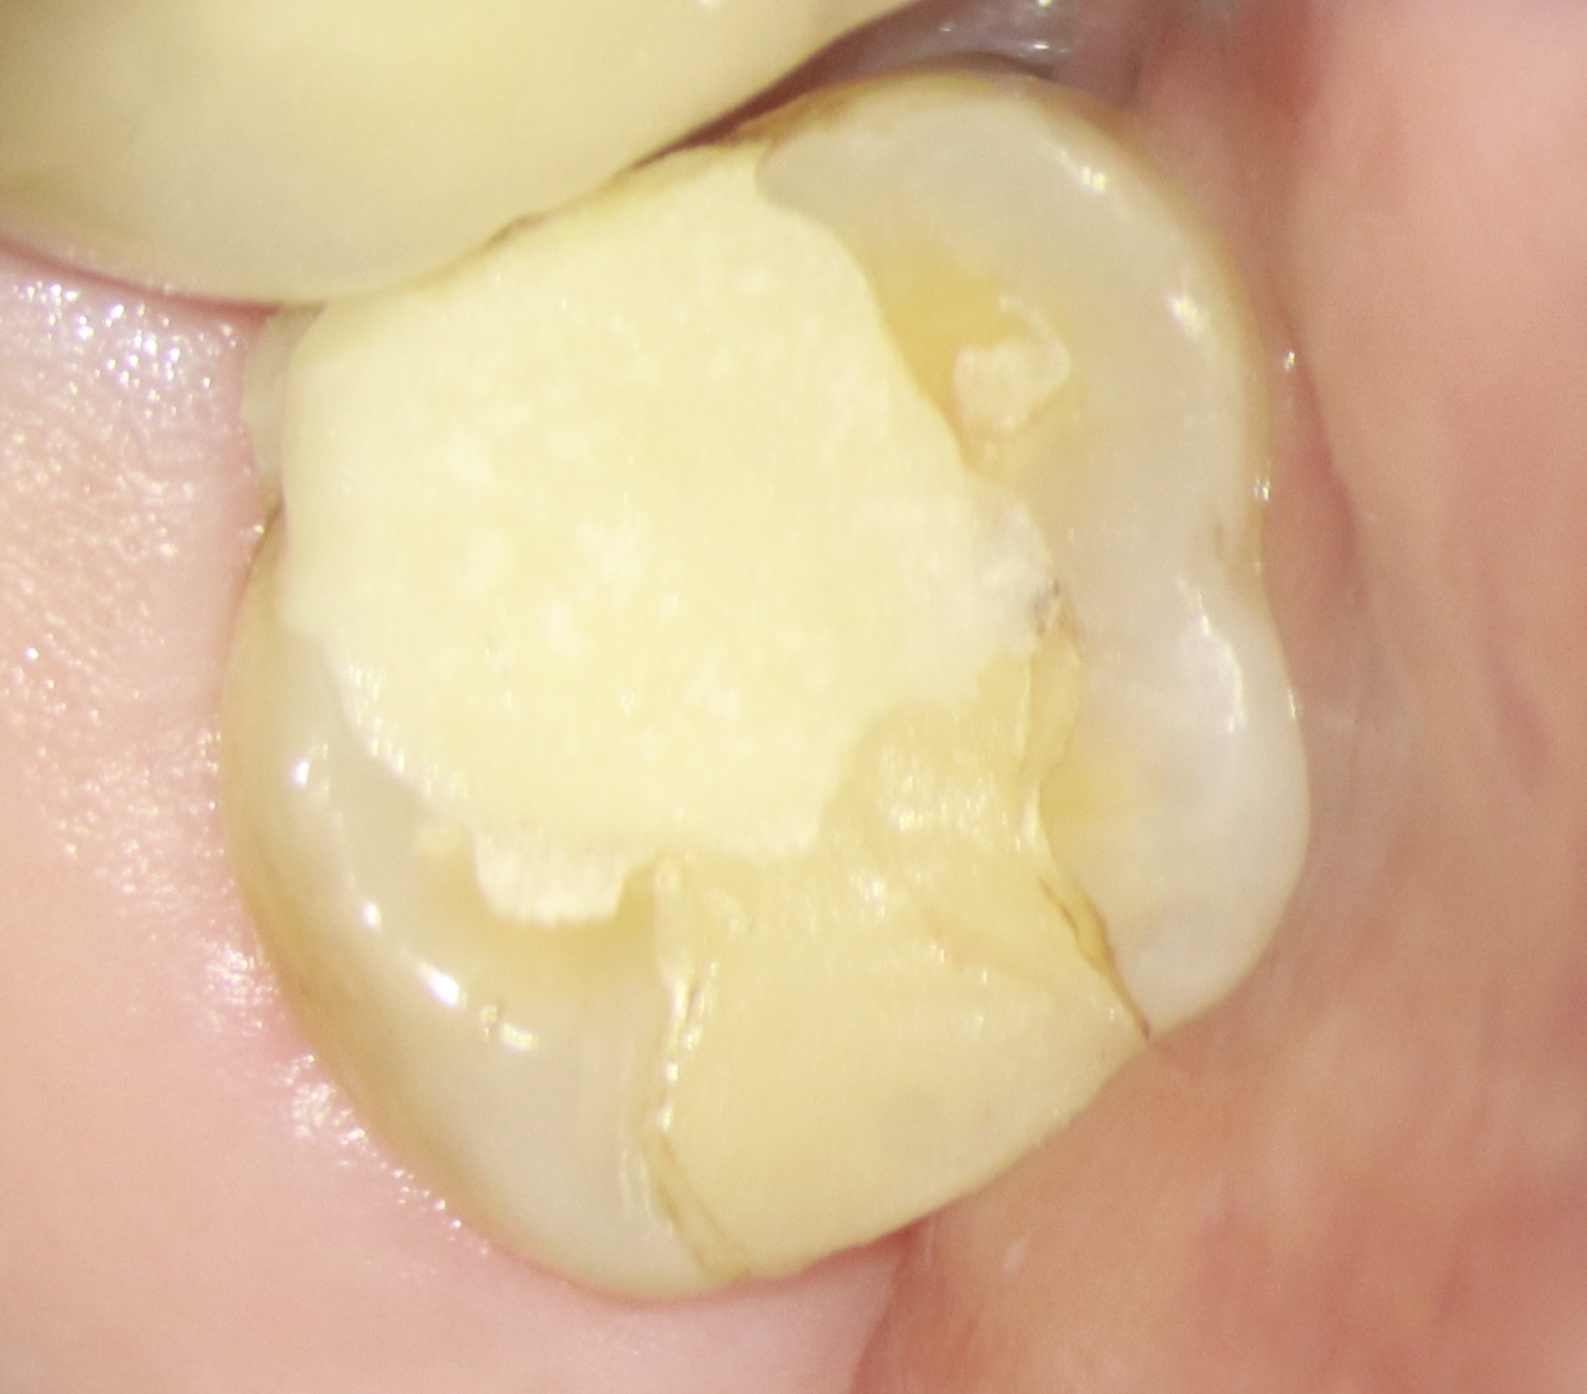

- Então, para a modelagem nos canais vestibulares, utilizou-se as limas 20.04 e 26/04 (Figura 4).

- Entretanto, o canal palatino por ser mais amplo foi instrumentado com a lima WaveOne Gold small, medium e large.

- Em seguida, os canais foram irrigados com hipoclorito de sódio 2,5% e foi utilizada a irrigação ultrassônica passiva para potencializar a limpeza dos canais.

- Para remoção do smear layer foi utilizado o EDTA.

- A obturação deu-se na técnica de onda contínua de condensação usando o cimento AHPLUS da Dentsply (Figuras 5, 6 e 7).

- Por fim, efetuou-se uma restauração em resina composta do acesso endodôntico e encaminhado o caso para o dentista indicador, para concluir os procedimentos restauradores e protéticos cabíveis.

Figura 2 Figura 3 Figura 4 Figura 5 Figura 6 Figura 7

Nota-se que o tratamento foi conservador, com pouco desgaste de dentina pericervical, dando mais longevidade e manutenção da integridade da estrutura dental.